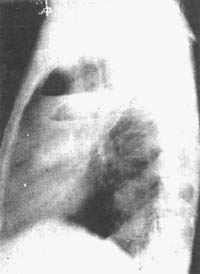

其他輔助檢查:X 線檢查:一般X 線胸部平片可獲得肺膿腫清晰影像,肺膿腫的X 線影像特點。